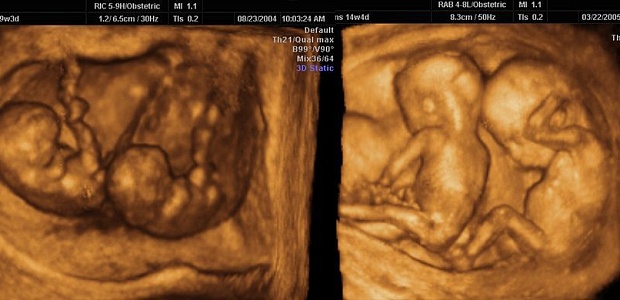

Узи плода в 3D-4D

4 000  Р

В сети клиник «Здоровье», в офисе на Советском, 24, будущие мамы могут сделать 3D и 4D УЗИ. Эта процедура является безопасной и информативной. При этом беременные женщины получат фото и видео будущего ребёнка на цифровой носитель.

Трехмерная реконструкция позволяет более чётко увидеть пороки лица, головы, визуализировать грыжевые выпячивания спинного мозга, передней брюшной стенки, пороки конечностей и аномалии позвоночника.